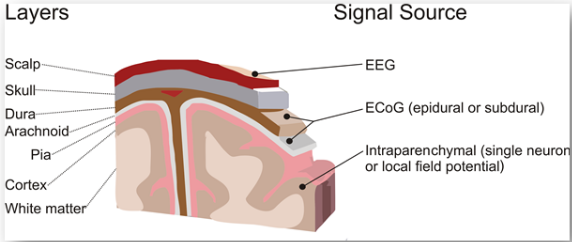

下图显示了大脑的不同层以及从中获取信号的位置。

非侵入式:采集EEG信号,将电极放在头皮上,也就是在最外层部分。

半侵入式:ECoG信号取自硬脑膜或蛛网膜上的电极。

侵入式(有创):将电极植入皮质,直接获取脑实质内信号。